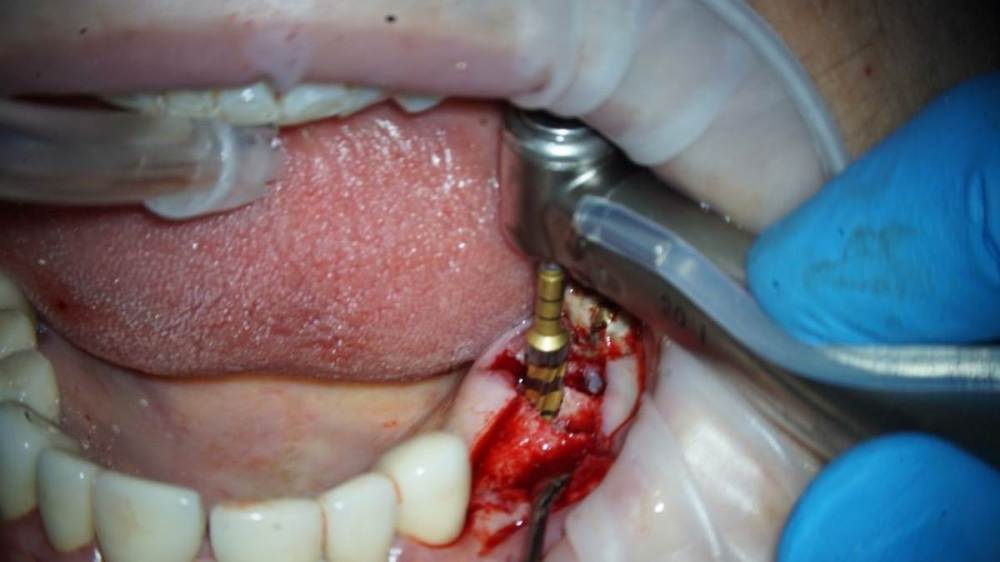

TIGER Опубликовано 11 августа, 2022 Поделиться Опубликовано 11 августа, 2022 Всем ? привет!закрытый синус через нави (шаблоны изготавливаю сам)и под контролем скопа,посадка на 12 часов всегда.и важно имплант с неагрессивным апексом ,преп ложа- проламывание дна фрезами DENSAH на реверсе 9 1 Ссылка на комментарий